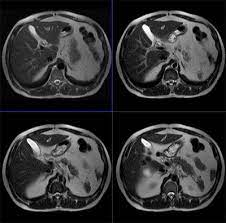

How will you get the test results? The mri of the abdomen will take approximately 60 minutes. What does the procedure involve? In some cases, it may take up to about 2 hours. Abdominal mris are used for a variety of reasons, such as examining:

What do i do after my scan? Newer scanners complete the process in less time. But the magnet is very powerful. In some cases, it may take up to about 2 hours. Do you have to drink anything before a mri scan? Most pelvis mri exams are done in the main hospital, acc or placer clinics. The mri of the abdomen will take approximately 60 minutes. How long to wait after mri? Abdominal mris are used for a variety of reasons, such as examining: How will you get the test results? Please contact the doctor who ordered the test for any test results. What are the risks of an mri of the abdomen? How to prepare for the test:

Please contact the doctor who ordered the test for any test results. In some cases, it may take up to about 2 hours. What do i do after my scan? The doctor who ordered the test will receive the results. How long does it take to get mri scan results? Do you have to drink anything before a mri scan? Newer scanners complete the process in less time. What are the risks of an mri of the abdomen? The images of your scan will be examined by a radiologist and the results will be sent to your referring physician who will review the results with you. Abdominal mris are used for a variety of reasons, such as examining: But the magnet is very powerful. How will you get the test results? Most pelvis mri exams are done in the main hospital, acc or placer clinics.